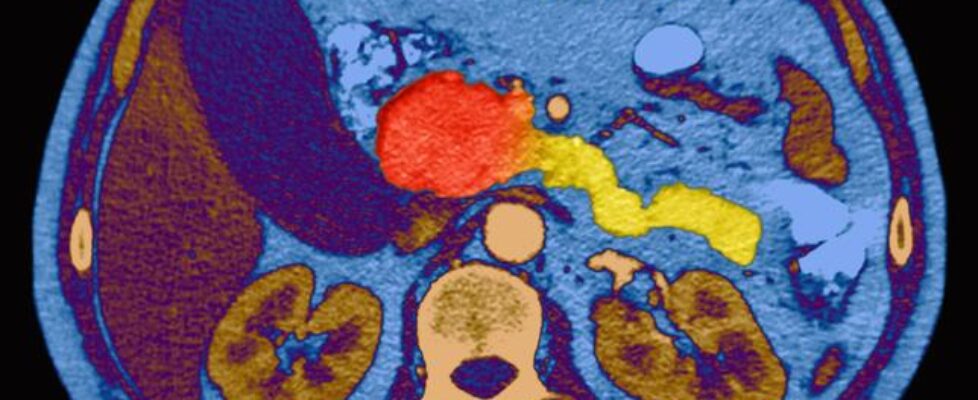

Cancer du pancréas : un candidat-médicament double la survie des patients

Une molécule innovante a permis à des malades en phase métastatique de voir leur espérance de vie doubler par rapport au groupe traité par la chimiothérapie standard. Du jamais-vu pour ces tumeurs très agressives.